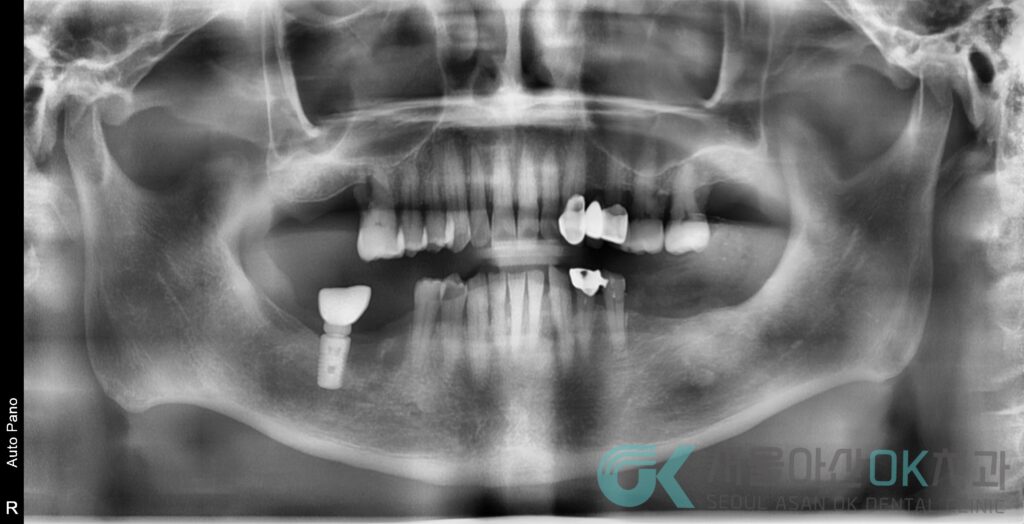

파노라마 촬영과 구내 사진으로 전체를 살펴보았습니다.

치조골이 전반적으로 낮아져 있는

수평적 골 소실이 동반된

만성 복합 치주염 소견이 확인되었습니다.

오래된 보철물 아래에서는

경계 불량과 2차 우식이 의심되었고,

하악 소구치 일부는

신경이 회복되지 않는 상태로

신경치료가 필요한 상황이었습니다.

또한,

이미 잇몸 지지가 많이 약해진 치아는

살리는 것보다 정리하는 것이 맞는 치아도 함께 존재했습니다.